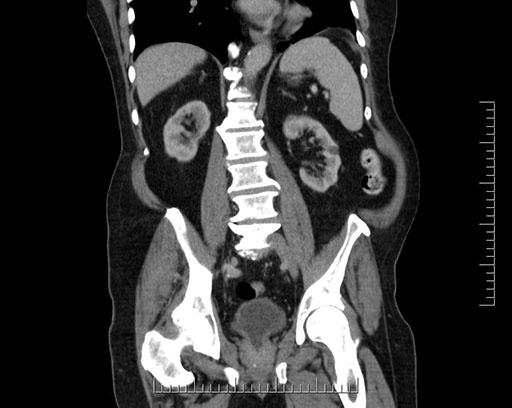

Imaging Analysis

Look through the patient's CT scan to identify any areas of concern for the necessary procedure.

Based on your CT findings, which issue(s) would give reason for "planned slowing down moment(s)" in this case?